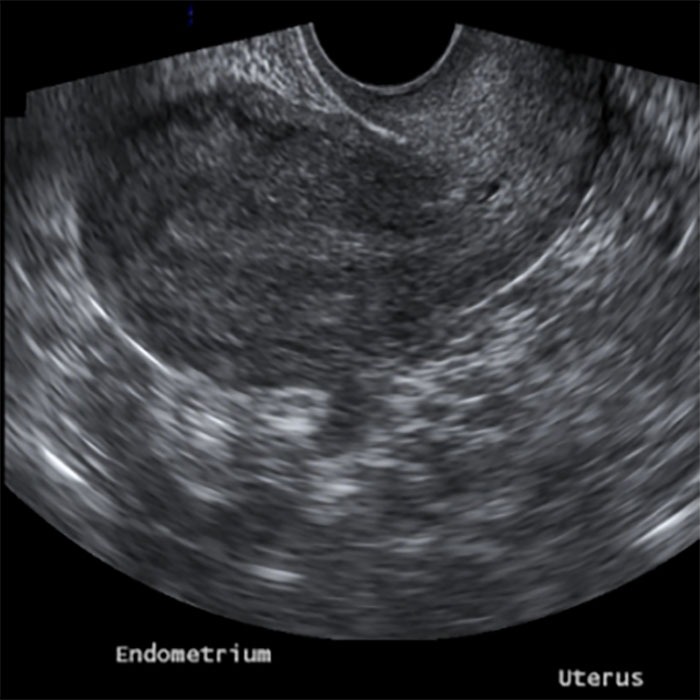

A Gynecologic / Pelvic Ultrasound is the preferred imagine modality in the study of the female pelvis, and provides important information in detecting and characterizing pelvic masses of uterine, ovarian, or adnexal origin. In patients with abnormal bleeding, transvaginal ultrasound helps in determining the presence of structural changes of the endometrium. Ultrasound plays a very important role in the evaluation of patients with acute pelvic pain. It allows identification of ovarian torsion, suspected ectopic pregnancy, ovarian cysts, and other pelvic conditions.